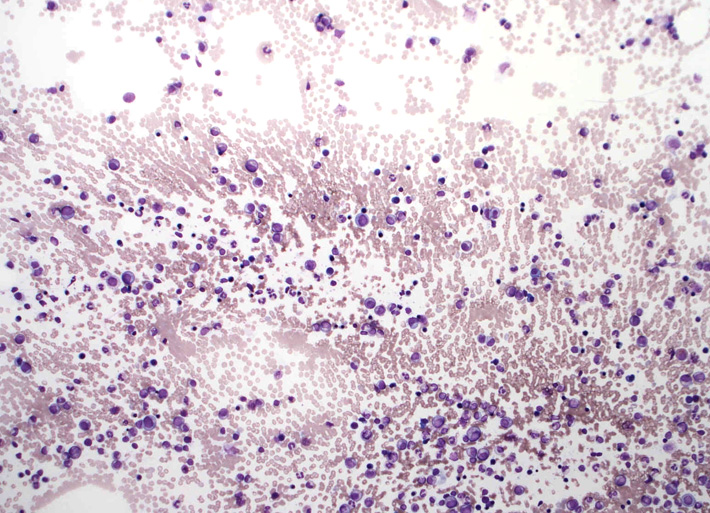

骨髄スメア標本です。ねっとりした血清成分がよくわかります。「hyperviscosity」の状態= 過粘稠(ねんちゅう-と読むらしい)症状; hyperviscosityの正しい訳は過粘度のほうがよいと思う.

赤血球が索状に連なる連銭形成rouleauxが明瞭です。